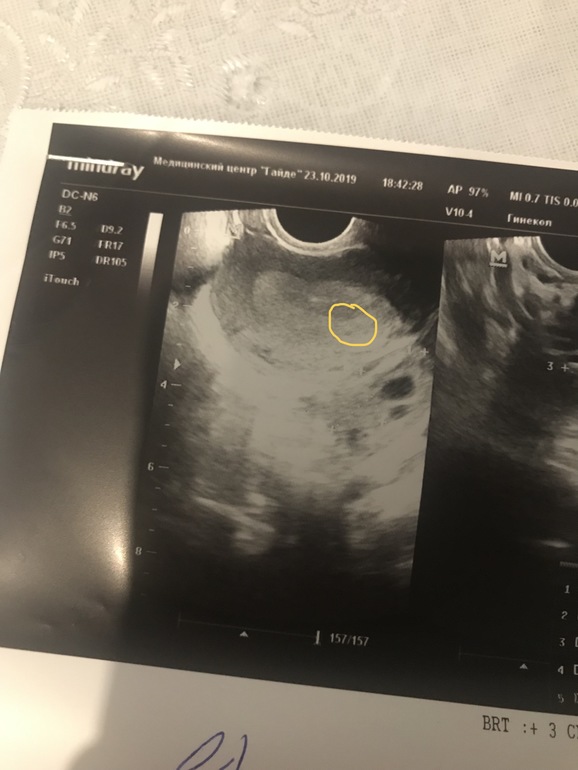

Вот это вот точечка в жёлтом кружке и есть...наша бусинка 💝крепись, родное сердце ❣ 23.10.2019 (33 ДЦ/19 ДПО)